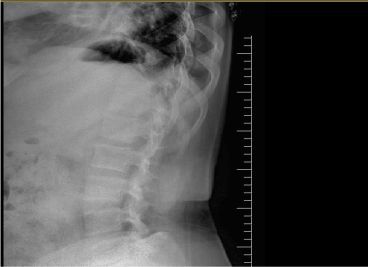

A forty-six-year-old woman was admitted to our outpatient clinic with complaints of inflammatory low back pain, widespread myalgia and knee arthritis episodes without fever that resolve spontaneously in 3-5 days. She was diagnosed with AS at age 43. Her medical history revealed mitral valvereplacement at 30 years of age due to rheumatic fever at 14 years of age. She had afamily history of FMF. On physical examination, she has not peripheral arthritis. Lumbar spinal motion was minimally limited. Sacroiliac provocation tests were positive. Chest expansion was normal. Her laboratory exam showed CRP 26 mg/L; ESR 22 mm/h. HLA B27 was negative. SAA was 3.02 mg/dl. Urine examination showed proteinuria. Genetic analysis confirmed aheterozygousmutationforM680I in theMEFVgene. X-rays indicated squaring of the lumbar vertebrae, and bilateral grade 2 sacroiliitis (Figure 1 and 2). She met diagnostic criteria for incomplete form of FMF [2]. She also met the criteria of ASAS [5]. We considered that it may be FMF spondylitis rather than the coexistence of AS and FMF. She received colchicum 0.5 mg three times daily. AFR, proteinuria and SAA were found to be normal.

Figure 1. Squaring of the lumbar vertebrae